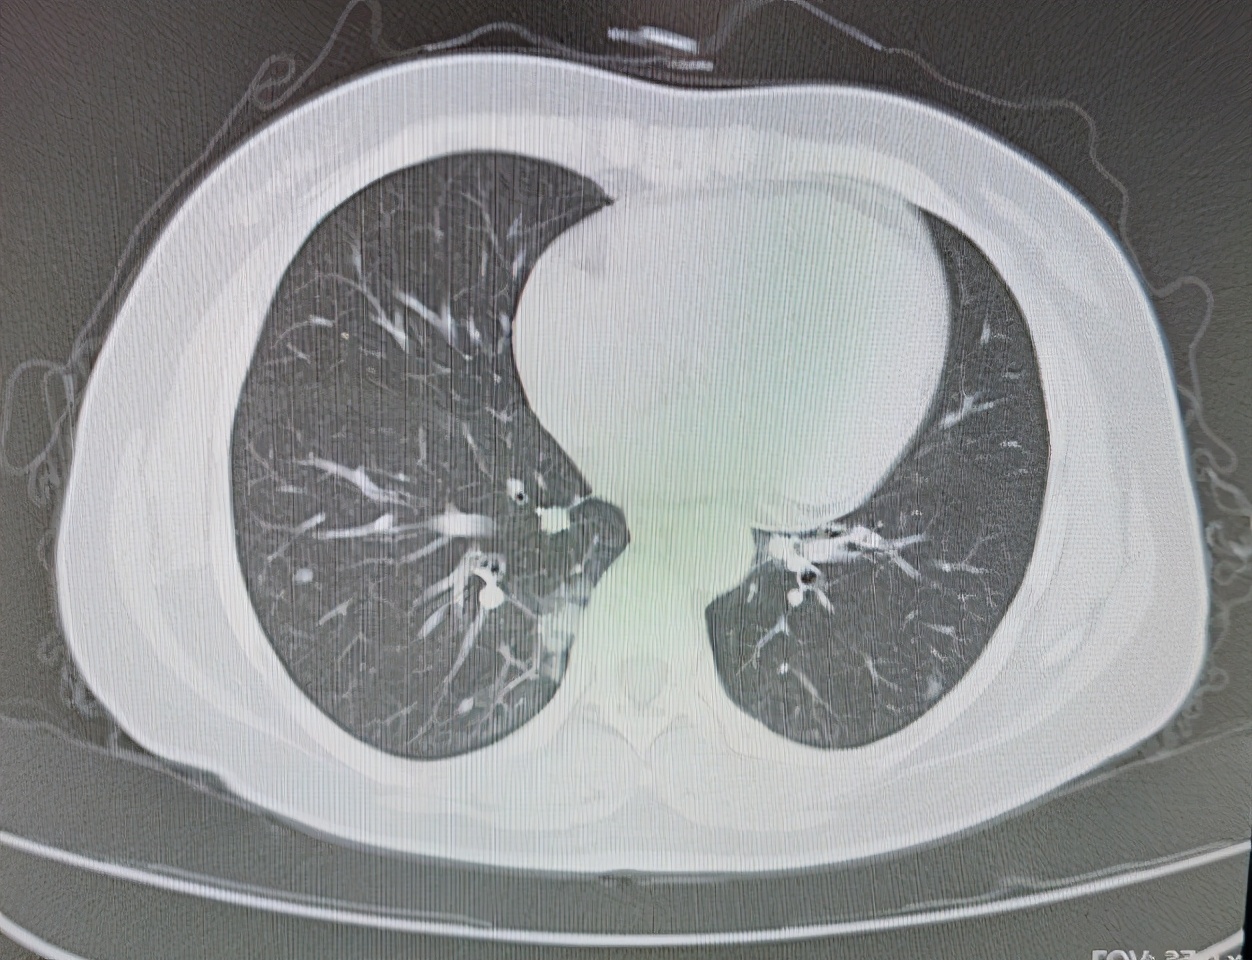

大爷姓李,2018年底无明显诱因出现间断咳嗽咳痰,受凉后加重,在我们医院诊断为慢性阻塞性肺病肺气肿慢性支气管炎,对症治疗后有所好转,其后定期复查,2019年6月在医院做胸部CT检查发现右肺有阴影。PET- CT检查提示,双肺多发结节及类结节影,部分结节葡萄糖代谢增高,考虑结核等肉芽肿性病变,当时患者没在意,后来又在我们医院做胸部增强CT提示,右肺下叶背段占位考虑恶性,建议穿刺,纵隔及右肺门区多发肿大,淋巴结考虑转移可能性大。

2020年1月,在CT引导下,肺主穿刺活检病理提示肺组织中可见肿瘤细胞呈巢团状排列,细胞有异型性,考虑为肺腺癌。知道得了肺癌,大爷从呼吸科转到肿瘤科挂了我的号,第一次来门诊乐呵呵地走进来,给我放了一袋子糖,说怕我看病人多,顾不上吃饭,含块儿糖别低血糖。

我耐心地给大爷和家属讲解着肺癌的情况和分期,大爷罹患的是非小细胞肺癌中的腺癌,已经有双肺及纵隔淋巴结转移,所以分期为四期,庆幸的是目前还没有其他脏器的转移,但是大爷的肺功能不好,有慢阻肺和肺气肿,所以在化疗的时候还需要严密监测肺功能,同时治疗慢阻肺和肺气肿的药物不能停,建议患者做一个EGFR靶标检测,看看后期是否能应用口服的靶向药物或者静脉抗血管生成的药物来控制病情。